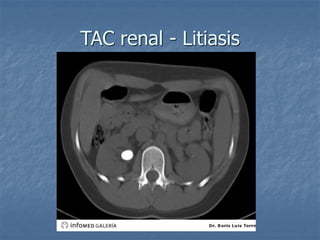

TAC renal - Litiasis

TAC renal -Litiasis